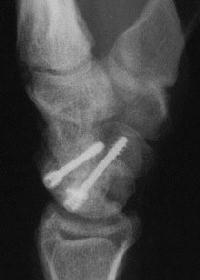

Case 4. Nonunion with a graft and screws placed in both directions from a single palmar approach, hyperextending the wrist for the proximal entry...

Click for larger image

and with the graft: